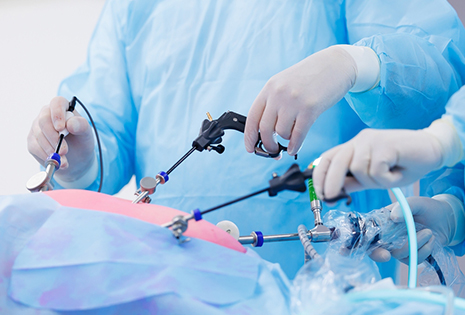

Experience the future of healthcare. Our state-of-the-art facilities are equipped with the latest

We offer complete women’s health and maternity care including antenatal checkups, normal and C-section deliveries, PCOS treatment, gynecological surgeries, postnatal support, lactation consultation, and now gastroenterology services too.

Yes. We have a dedicated gastroenterology department for treating digestive issues like acidity, piles, constipation, liver problems, and more.